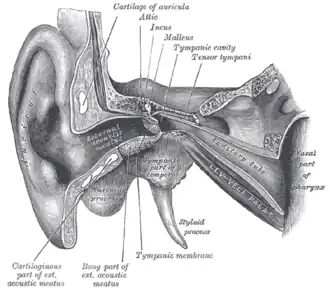

_with_label.png) Right temporal bone and mandible (styloid process labeled at bottom) | |

External and middle ear, opened from the front. Right side. (Label for styloid process is bottom center.)

External and middle ear, opened from the front. Right side. (Label for styloid process is bottom center.) -